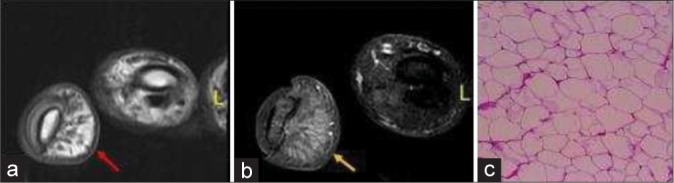

Soft tissue tumors involving the hand are common and most often benign. It is important to know the spectrum of soft tissue tumors of the hand and understand the typical as well as atypical imaging features are seen on different imaging modalities. The imaging features are largely determined by the tumor histopathology; thus, the basic idea about the tumor histopathology will always be useful. This article intends to focus on a comprehensive approach including demographics, clinical presentation, and imaging findings required to diagnose the tumor definitely or narrow the differentials. This article discusses common soft tissue tumor mimics of the hand as well, however, excludes the bone tumors for the sake of brevity.